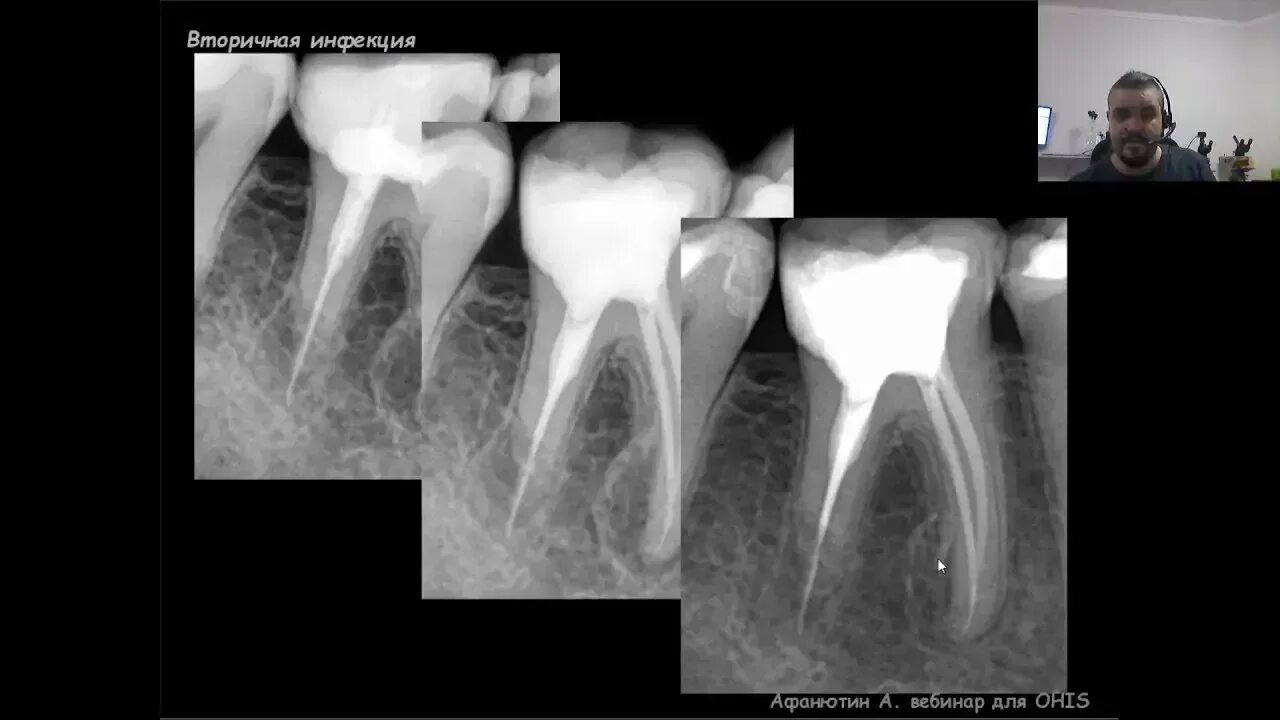

Ретроградное пломбирование корневых